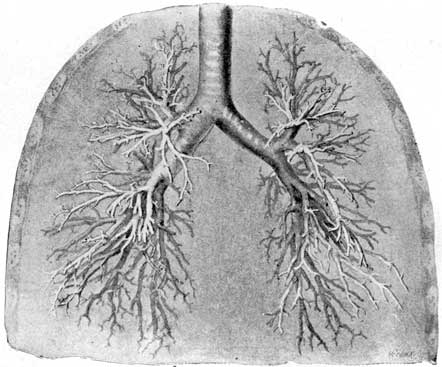

| 10. Trachea and bronchial tubes | 45 |

| 11. Heart, lungs, and diaphragm | 45 |

Fig. 10 (Spalteholz). A view of the lower part of the trachea, dividing into the main bronchial tubes, which again branch into a tree-like form. The air-cells are built up around the terminations of the finest bronchial tubes, of which they are a sort of membranous extension.

Fig. 11 (Spalteholz). Shows well the relations of heart, lungs, and diaphragm. The lungs have been drawn back, otherwise the heart would be covered almost wholly by them. It will be noted that the heart-covering is attached to the diaphragm. The fact that the stomach and other important organs of the abdomen lie immediately beneath the diaphragm is a significant one for the voice-user. Manifestly, a full stomach and free, vigorous breathing are incompatible.